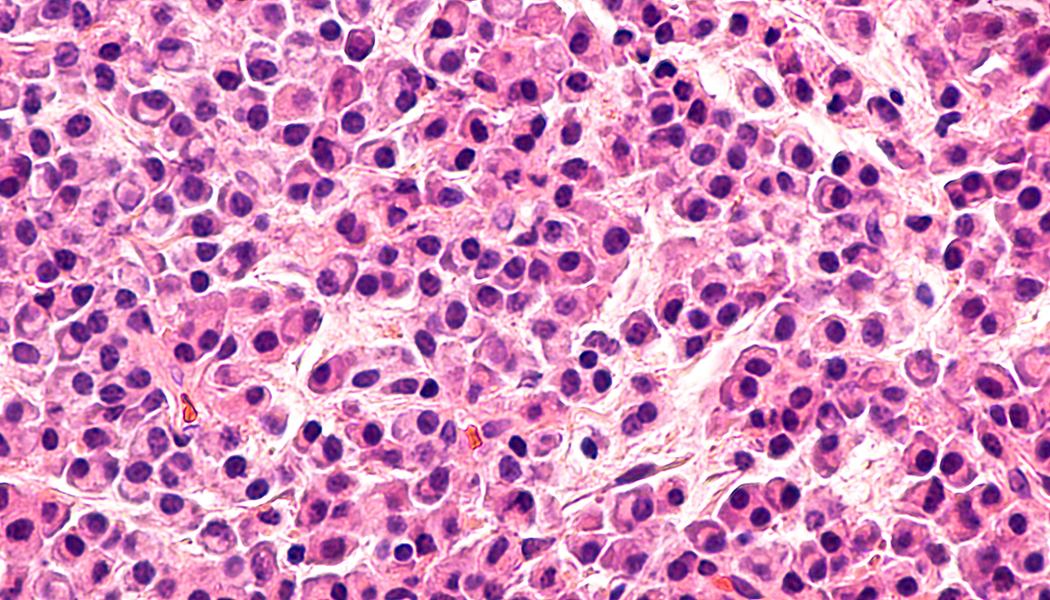

Multiple myeloma (MM) is a bone marrow cancer that affects plasma cells. Bone marrow is the soft and spongy tissue which resides in the cavities of many of our bones. It is rich in cells which produce new blood cells. On average, 500 billion new blood cells are produced each day within the bone marrow. These cells can be categorized as either lymphoid (producing lymph cells) or myeloid (producing red blood cells, white blood cells (including plasma cells) and plasma). Normally, plasma cells work as part of the immune system to produce antibodies which can recognize and neutralize pathogens; but in MM, these cells become cancerous and grow out of control, leading to multiple painful bone tumors, as well as anemia, kidney failure and recurrent infections. MM relapse rates are quite high because of the inherent challenge of immunosuppression, given that the immune system itself is directly compromised. As a result, immunology has been a major focus of new treatment methods.

Professionals are now able to effectively predict how each patient will respond to different treatment methods for MM. This ground-breaking discovery is capable of changing the face of MM intervention by increasing patient outcomes and improving the understanding of the mechanisms behind treatment failure. This predictive computational mapping is achieved through genomic database information calculations. These calculations can look at the various drug interactions and their impact on the cell signaling and metabolism of many different MM phenotypes. The phenotypes of patient’s tumors are determined through tumor biopsies. This information is then entered into the computational modelling system where a variety of drug interactions and doses can be tested to see what specific modulating chemicals will most effectively target the specific form of MM which is present.